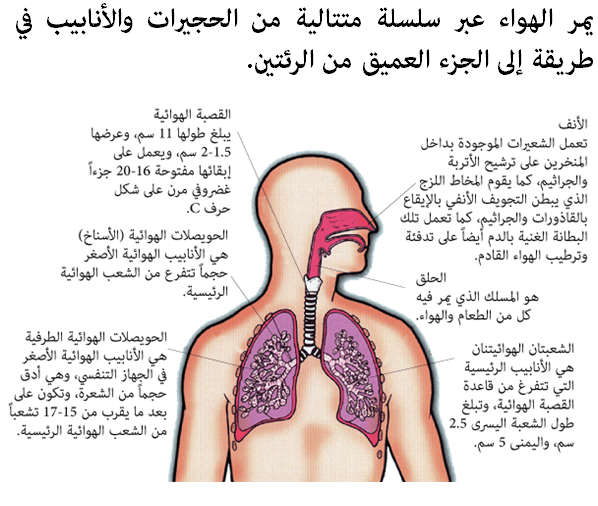

أنفُث، إِلهث، إلى الداخل، إلى الخارج، خذ شهيقاً، أخرج زفيراً… تقوم منظومة التنفس الخاصة بالجسم، أو الجهاز التنفسي، بالحصول على العنصر الحيوي بالنسبة له، وهو الأكسجين، من الهواء المحيط ونحن نحتاج إلى الأكسجين الذي يلعب دوراً في كيمياء الجسم، إذ يقوم بتجزئة سكر الدم (الجلوكوز)، وإطلاق الطاقة الموجودة به، والتي تزود بالقوة جميع العمليات الحيوية والأنشطة التي يؤديها الجسم تقريباً. والأجزاء الرئيسية للجهاز التنفسي هي: الرئتان، واللتان يتم الوصل إليهما عبر سلسلة متتالية من المسالك الهوائية التي تؤدي بنا إلى الأسفل عبر الأنف، والحلق، والقصبة الهوائية.

المسالك الهوائية المتفرعة

تبادل منصف

تكون المواضع التي يفد إليها الأكسجين الذي يتم إدخاله إلى الجسم على شكل فراغات ضئيلة الحجم تتخذ شكل الفقاقيع، وتوجد في عمق بداخل الرئتين، ويُطلق عليها اسم «الحجيرات الهوائية أو الأسناخ».

• تنشأ الحجيرات الهوائية في نهايات المسالك الهوائية الأصغر حجماً والتي تُعرف بالحويصلات الهوائية الطرفية.

• يوجد ما يقرب من 250 – 300 مليون حجيرة هوائية في كل رئة.